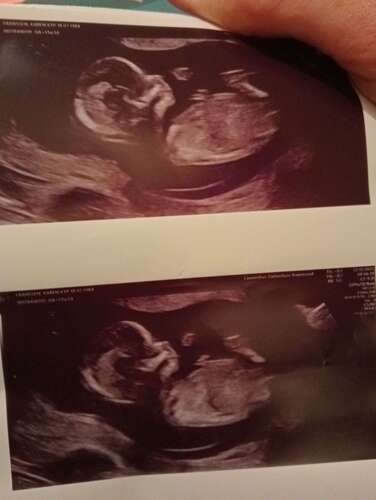

Afgelopen dinsdag de 13 weken echo gehad van ons 🫶🏼je. We hebben 2 hele mooie foto’s mee gekregen en de rest van de foto’s is op een usb stick gezet, eenmaal thuis aangekomen snel de usb stick in de laptop gestopt! Wat bleek de lieve dame had een kort filmpje gemaakt waarbij ons dotje aan het duimen was 🥰 zo verliefd!